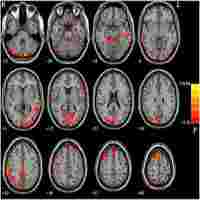

| Abstract | Background Although symptoms of depressive episodes in patients with bipolar depressive episodes (BDE) and major depressive disorder (MDD) are similar, the treatment strategies for these disorders are completely different, suggesting that BDE and MDD have different neurobiological backgrounds. In this study, we examined the relationship between brain function and clinical symptoms, particularly cognitive function, in female individuals with bipolar disorder and MDD experiencing depressive episodes. Methods Regional homogeneity (ReHo) was analyzed in 51 medication-free female patients with BDE, 63 medication-free female patients with MDD, and 45 female healthy controls (HCs). Depressive symptom severity was assessed using the 24-item Hamilton Depression Rating Scale (HAMD-24), and multidimensional cognitive function was evaluated using the MATRICS Consensus Cognition Battery. Partial correlation analysis was used to explore the links between the brain regions and clinical characteristics. A support vector machine (SVM) was used to assess the classification accuracy. Results Compared with HCs, patients with BDE and MDD had decreased ReHo in the left lobule VI of the cerebellum and increased ReHo in the left precuneus. Patients with BDE also had reduced ReHo in the left lobules IV–V of the cerebellum and increased ReHo in the right putamen, unlike patients with MDD who had no significant differences in these regions. Patients with BDE exhibited more severe cognitive deficits in processing speed, attention, word learning, and overall cognitive function than those with MDD. In patients with BDE, a significant negative correlation was found between the right putamen and HAMD-24 scores. However, no significant association was observed between abnormal ReHo levels and cognitive function. The SVM effectively differentiated between patients with BDE, MDD, and HCs. Conclusion Cognitive impairment was more severe in female patients with BDE than in those with MDD. Changes in the ReHo values of the right putamen and left lobules IV–V may serve as unique neuroimaging markers for BDE. Alterations in the ReHo values of the left precuneus and left lobule VI could serve as common pathophysiological mechanisms for BDE and MDD in women and indicate depressive states. |